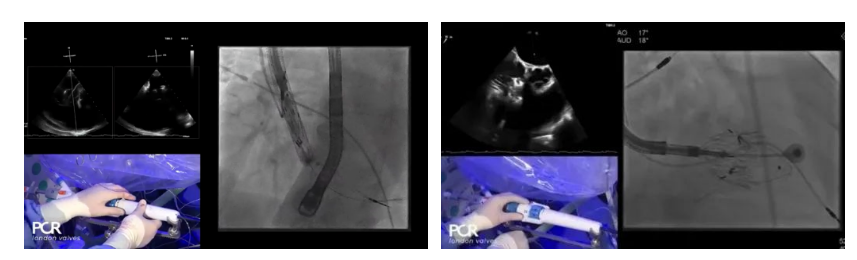

在Thomas Modine教授的線上指導(dǎo)下,德國Mainz中心Ralph Stephan von Bardeleben教授完成了LuX-Valve Plus經(jīng)血管三尖瓣置換系統(tǒng)在其所在中心的首例植入,術(shù)后Stephan教授高度贊揚LuX-Valve Plus人工三尖瓣瓣膜“植入過程高度可控,安全有效”。接受治療的是一例82歲的高齡男性患者,術(shù)前NYHAⅢ級,因復(fù)發(fā)心衰入院,有逾5年的慢性房顫病史。這例患者因特殊的解剖結(jié)構(gòu)以及較大的三尖瓣瓣環(huán),有起搏器植入史,被所有其他經(jīng)導(dǎo)管三尖瓣修復(fù)或置換器械的臨床排除在外,因此等了一年半才等到此次LuX-Valve Plus的手術(shù)機會,實屬不易。

手術(shù)在全麻狀態(tài)下開展,采用經(jīng)右側(cè)頸靜脈入路的方式將輸送器送入患者心臟內(nèi),在TEE及DSA引導(dǎo)下調(diào)整輸送器頭端角度,使得輸送器與三尖瓣瓣環(huán)平面垂直。在輸送器進入右心室后釋放室間隔錨定裝置,而后釋放瓣葉夾持件(2個耳片結(jié)構(gòu))成垂直狀態(tài)。在TEE及DSA確定夾持件固定至三尖瓣葉根部且位于右室側(cè)后釋放人工瓣心房側(cè)盤片。隨后調(diào)整瓣膜同軸性以及室間隔錨定件位置(貼合室間隔),前推藏針管并固定,進而釋放室間隔錨定裝置,并再次確認瓣膜位置、穩(wěn)定性及同軸性,合攏輸送鞘后撤出輸送器,完成LuX-Valve Plus人工三尖瓣瓣膜的植入。